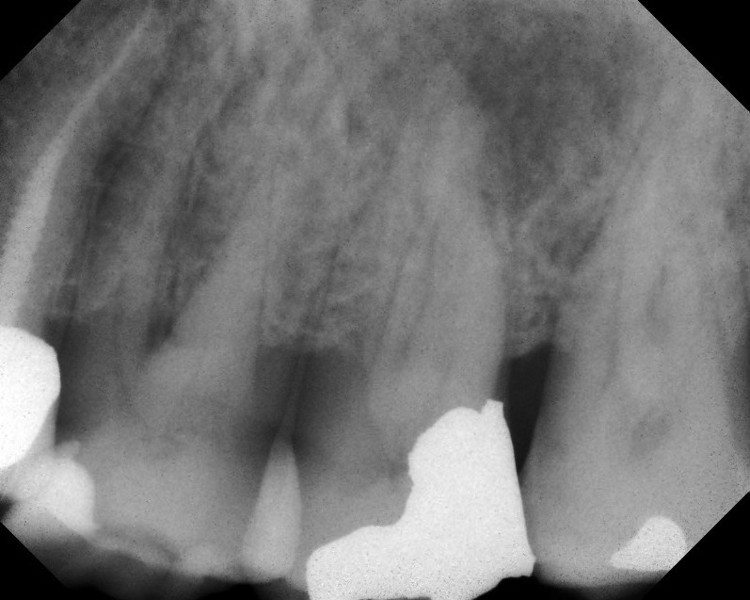

Isolierung mittels Kofferdam.Elektonische Längenbestimmung und Digitalen Rö-Messaufnahme.Präparation mit rotierende NiTi-Instrumente und Motoren mit Drehmomentbegrenzung. Strenge aseptische Behandlungsstrategie: Steriles Instumentarium, intensive desinfizierende Spülungen ultraschallaktiviert, medikamentöse Desinfektion mittels Kalziumhydroxid und Chlorhexidin und dichter koronaler Verschluss mit der Dentinadhesiv Technik.

Die 3D Wurzelfüllung mit erwärmter Guttapercha ( vertikaler Kondensation) One Step Obturator ( Soft-Core) Thermafil oder  Downpack/ Backfill Methode (CW nach Buchanan )sind meine Standard-Techniken.

Digitales Röntgen wurde 2006 zur Strahlungsreduktion und Qualitätssicherung eingeführt !